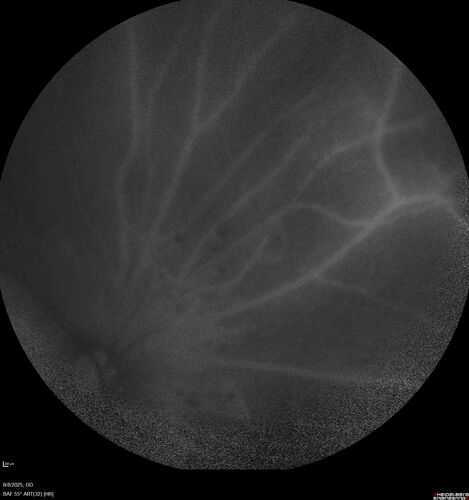

NPDR and Severe macular ischemia sudden vision loss

60 year old female with sudden vision loss OD 1 week ago. VA 20/63, 20/200. OCT-A and FA shows severe macular ischemia OU